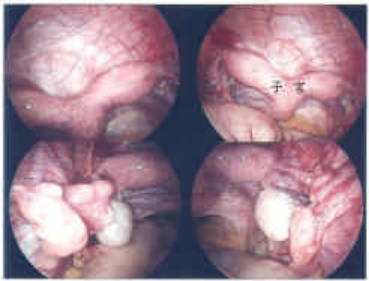

38 一位 28 歲女性已有一個半月月經沒來,近兩日常感覺右下腹疼痛,今日則因疼痛加劇而就醫,經陰 道指診發現子宮有觸壓疼痛的情形,同時子宮右邊處亦有觸壓疼痛的情形。尿液懷孕試驗呈現陽性反應,超音波掃描發現右邊卵巢(ROV)旁有囊狀腫塊,大小約 2.5×2.8 公分(箭頭所指之處), 此患者最適合之診斷為:

(A)輸卵管外孕(tubal pregnancy)(B)卵巢腫瘤(ovarian tumor)(C)輸尿管水腫(hydroureter)(D)輸卵管卵巢膿瘍(tubo-ovarian abscess)